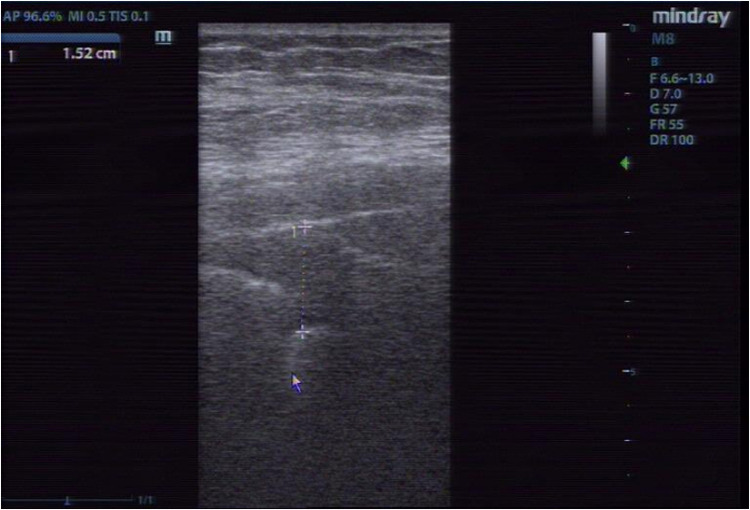

Objective: To investigate the diagnostic value of bedside lung ultrasound and chest computed tomography (CT) for subpleural lesions and lung consolidation in intensive care unit (ICU) patients with severe pneumonia.

Methods: A retrospective selection was made of 100 ICU patients with severe pneumonia who were treated in our hospital from June 2020 to July 2024 as the research subject group. All patients underwent bedside lung ultrasound and chest CT examinations, and the CT imaging manifestations of the patients were observed. Using the CT examination results as the gold standard, the patients were divided into the lung consolidation group and non-lung consolidation group. The relevant data were collected and the clinical data of the two groups were observed. The positive predictive value, negative predictive value, specificity, sensitivity and accuracy of bedside lung ultrasound in the diagnosis of subpleural lesions and lung consolidation were analyzed.

Results: Chest CT showed that 73.00% of the patients had ≥2 lung lobes involved, mainly in the right lung (61.00%). 56.00% patients had 1-2 organs involved, mainly kidney (77.00%) or heart (87.00%). 69.00% of patients had pulmonary consolidation, 86.00% had bronchial shadow, and 82.00% had mass, patchy or nodular shadow. Compared with the non-lung consolidation group, the lung ultrasound score of the lung consolidation group was significantly increased (P<0.05), and the proportion of lung parenchyma, the number of subpleural lesions and the number of pleural intercostal changes were significantly increased (P<0.05). The consistency test showed that bedside ultrasound had a high consistency with chest CT in the diagnosis of subpleural lesions and lung consolidation (Kappa=0.678, P<0.05; Kappa=0.743, P< 0.05).

Conclusion: Bedside lung ultrasound and chest CT had a high consistency in the diagnosis of subpleural lesions and lung consolidation, which may be used as an important method to judge the development of severe pneumonia in ICU.